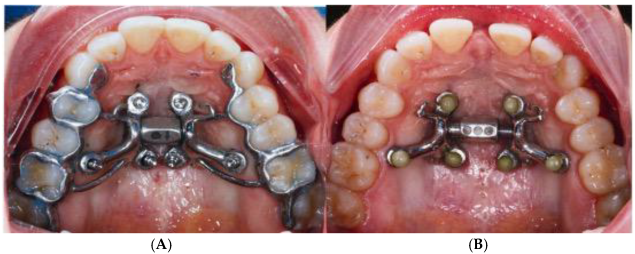

2.5. Case B: Guide-Assisted Midpalatal Piezocorticotomy

2.6. Case C: Bilateral Posterior Crossbite with Guide-Assisted Expansion